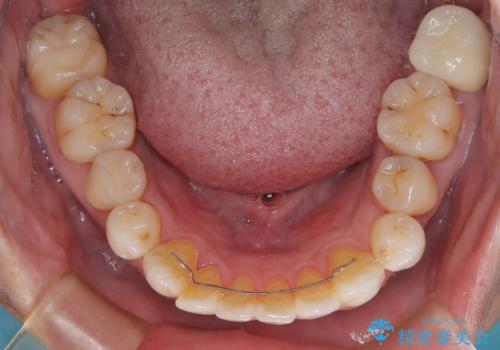

その他は銀歯のインレー(部分的な詰め物)が装着されており、それらはむし歯を除去した後にセラミックインレーにて修復治療を行い、左下と根管治療を行う左上の奥歯はオールセラミッククラウンにて補綴治療を行うこととしました。

根管治療の途中で、矯正治療の後戻りが気になるとのことで、下顎前歯の叢生を改善するためにマウスピース矯正を並行して行いました。

目立っていた銀歯がなくなり、患者様には大変満足していただけました。